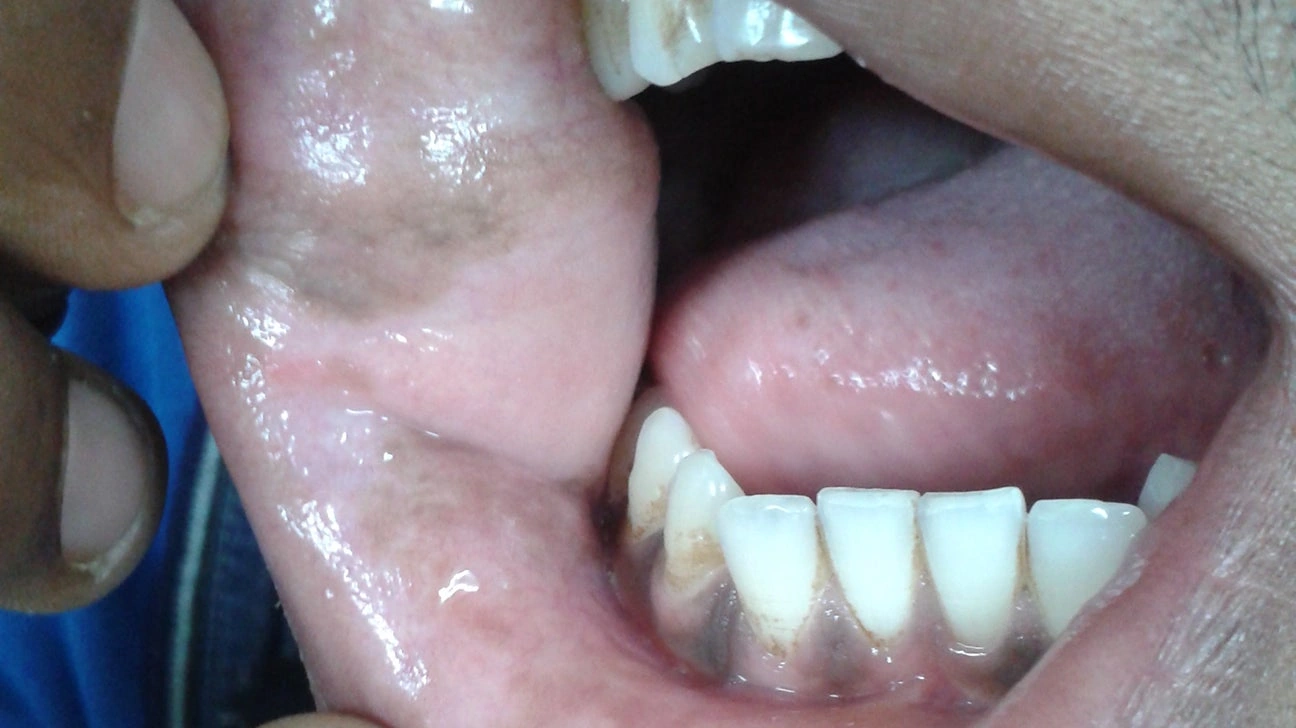

(img by Cape Dental Care) Wait, What’s That Spot? Ever had that moment where you’re happily brushing away, singing along in your head, then suddenly… you glance in the mirror and spot a tiny, dark mark on your gums? Happens to the best of us—I’m not kidding. I remember the first time it happened to […]

What’s That Spot? Let’s set the scene. You’re brushing your teeth on some random Tuesday, humming along to your favorite playlist… then you spot it in the mirror. A tiny black or brown dot inside your cheek, maybe on your gum or tongue. It’s easy to freeze—are you seeing things? Is it serious? Or, is […]